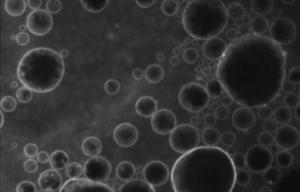

HÉROINE : Un vaccin prometteur, et contre la dépendance aux opioïdes aussi

Actualité publiée le 19/12/2017PHARMACOCINÉTIQUE: Des bulles lipidiques pour franchir la barrière hémato-encéphalique